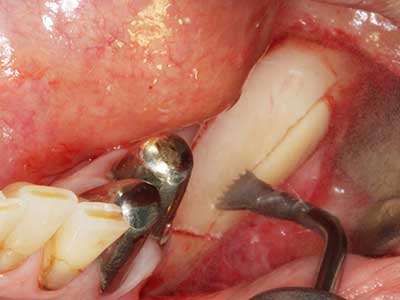

Si es preciso realizar intervenciones quirúrgicas en las que el hueso está en contacto directo con estructuras sensibles, como son los vasos sanguíneos o los nervios, los instrumentos rotativos presentan un enorme potencial de provocar lesiones iatrogénicas. Así, precisamente en la representación de nervios después de una lesión iatrogénica, o en el transcurso de la lateralización de un nervio para resecciones, reconstrucciones o incorporación de implantes, los equipos piezoeléctricos pueden resultar muy útiles para preparar la tapa ósea y retirar las partes de tejido duro cercanas al nervio (fig. 17-20). Por lo general, un ligero contacto del cordón nervioso con el inserto piezoeléctrico no tiene consecuencia alguna; ahora bien, un procedimiento poco cuidadoso con movimientos tipo sierra o piezas de trabajo sobre la base ósea aún existente puede provocar lesiones nerviosas temporales o incluso permanentes. Con todo, el riesgo de sufrir una lesión de este tipo se considera significativamente inferior que en los casos en los que se utilizan sierras y fresas (Pereira, Gealh et al. 2014).